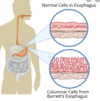

In Barrett’s Oesophagus the cells lining the lumen at the distal end of the oesophagus undergo metaplasia, which is the replacement of one cell type to another from the basal cells due to a stimulus. The normal non keratinising stratified squamous epithelium of the lower oesophagus undego metaplasia and become what type of cell and why this type of cell?

- columnar cells

- more equipped to protection of organ such as in the intestines

In the image below of the oesophagus we can see where metaplasia has occured and there has been a switch from non keratinising stratified squamous epithelium to column cells. Which number in the image below related to squamous and columnar cells?

1 = columnar cells

2 = non keratinising stratified squamous epithelium